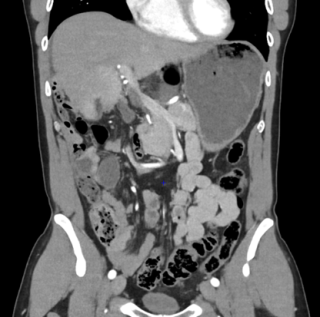

A 37-year-old man with an history of cirrhosis and atrial fibrillation treated with apixaban was admitted for weakness and dizziness. On admission, he was hypotensive and tachycardic, with signs of peripheral hypoperfusion and diffuse abdominal tenderness. Laboratory investigations revealed severe anemia (Hb 46 g/L), marked coagulopathy, and metabolic acidosis with elevated lactate levels. Abdominal CT scan demonstrated a left flank mesenteric lesion exerting mass effect on adjacent small bowel loops, associated with a large-volume acute hemoperitoneum. Emergency exploratory laparotomy revealed approximately 4 liters of hemoperitoneum and a large jejunal intramural hematoma with complete serosal rupture. Segmental jejunal resection was performed with temporary abdominal closure. A planned second-look laparotomy allowed jejunojejunal anastomosis. Histopathological examination confirmed a submucosal hematoma with preserved mucosa and no evidence of ischemia.